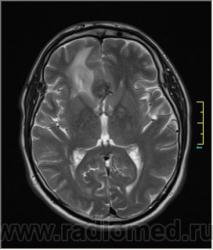

Ax T2:

Иначе говоря, аневризма с хронической геморрагией, т.к. мы видим фракции крови различного возраста.

Постепенное пристеночное образование тромбов приводит к появлению типичного для аневризмы феномена -слоистости МР сигнала в полости аневризмы. Данная картина демонстрирует слоистый характер тромботических масс в полости аневризмы .Функционрирующая часть имеет низкий сигнал во всех режимах сканирования. Дополнительно-перифокальный отек.

А может более корректно интерпретировать как частично тромбированная аневризма... Уж коь речь идет о фракциях, ну то есть о тромбе по сути.... Ну и плюс перфокальный отек головного мозга (вероятнее цитотоксический+вазогенный).